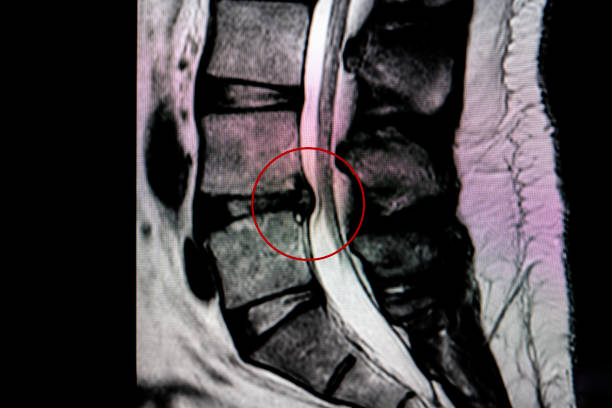

추간판 탈출증 디스크 제거 수술은 주로 디스크의 손상된 부분을 제거하는 것을 포함하며 디스크로 인해 신경의 압력을 완화하는 데 주로 사용됩니다.

척추 내시경 수술

추간판 탈출증 수술은 수술후 통증이나 재발과 같은 합병증이 나타날 수 있어 최소침습적인 수술 방법들이 발전되고 있습니다. 척추 내시경 수술은 피부에서 디스크까지 내시경을 이용해 접근하여 디스크를 제거하는 치료법으로, 보존요법과 수술요법 사이의 최적의 방법입니다. 일상생활 복귀가 빠르고 출혈이 거의 없어 수혈도 필요가 없습니다. 보통 국소 마취로 진행됨으로 전신마취의 위험이 있는 고령자나 당뇨병 환자에게서도 시행할 수 있다는 장점이 있습니다.